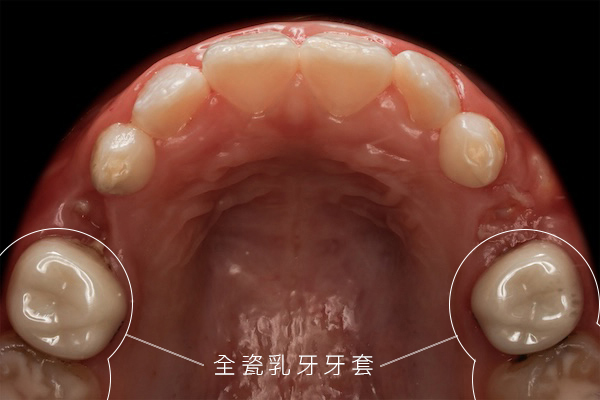

上鏡無死角:全瓷美學牙冠

「考量努拉平時有上鏡需求,這次在修復方式的選擇上,我們特別重視整體美觀的呈現。」陳醫師特別提到,由於努拉的蛀牙位置較偏前側,為了維持自然的視覺感,這次捨棄了傳統的銀色小鋼牙,改選全瓷美學牙冠修復。這不僅提供了極高的硬度保護,色澤也與原生牙完美融合,讓努拉醒來後依然能大方展現笑容。

Camera-Ready: Aesthetic All-Ceramic Crowns "Considering Nuala’s need to be on camera, we placed special emphasis on the overall aesthetic presentation when choosing the restoration method." Dr. Chen specifically mentioned that because Nuala's cavities were closer to the front, they ditched traditional silver "stainless steel crowns" in favor of aesthetic all-ceramic crowns to maintain a natural look. These provide high-strength protection and blend perfectly with her natural tooth color, allowing Nuala to smile confidently as soon as she woke up.